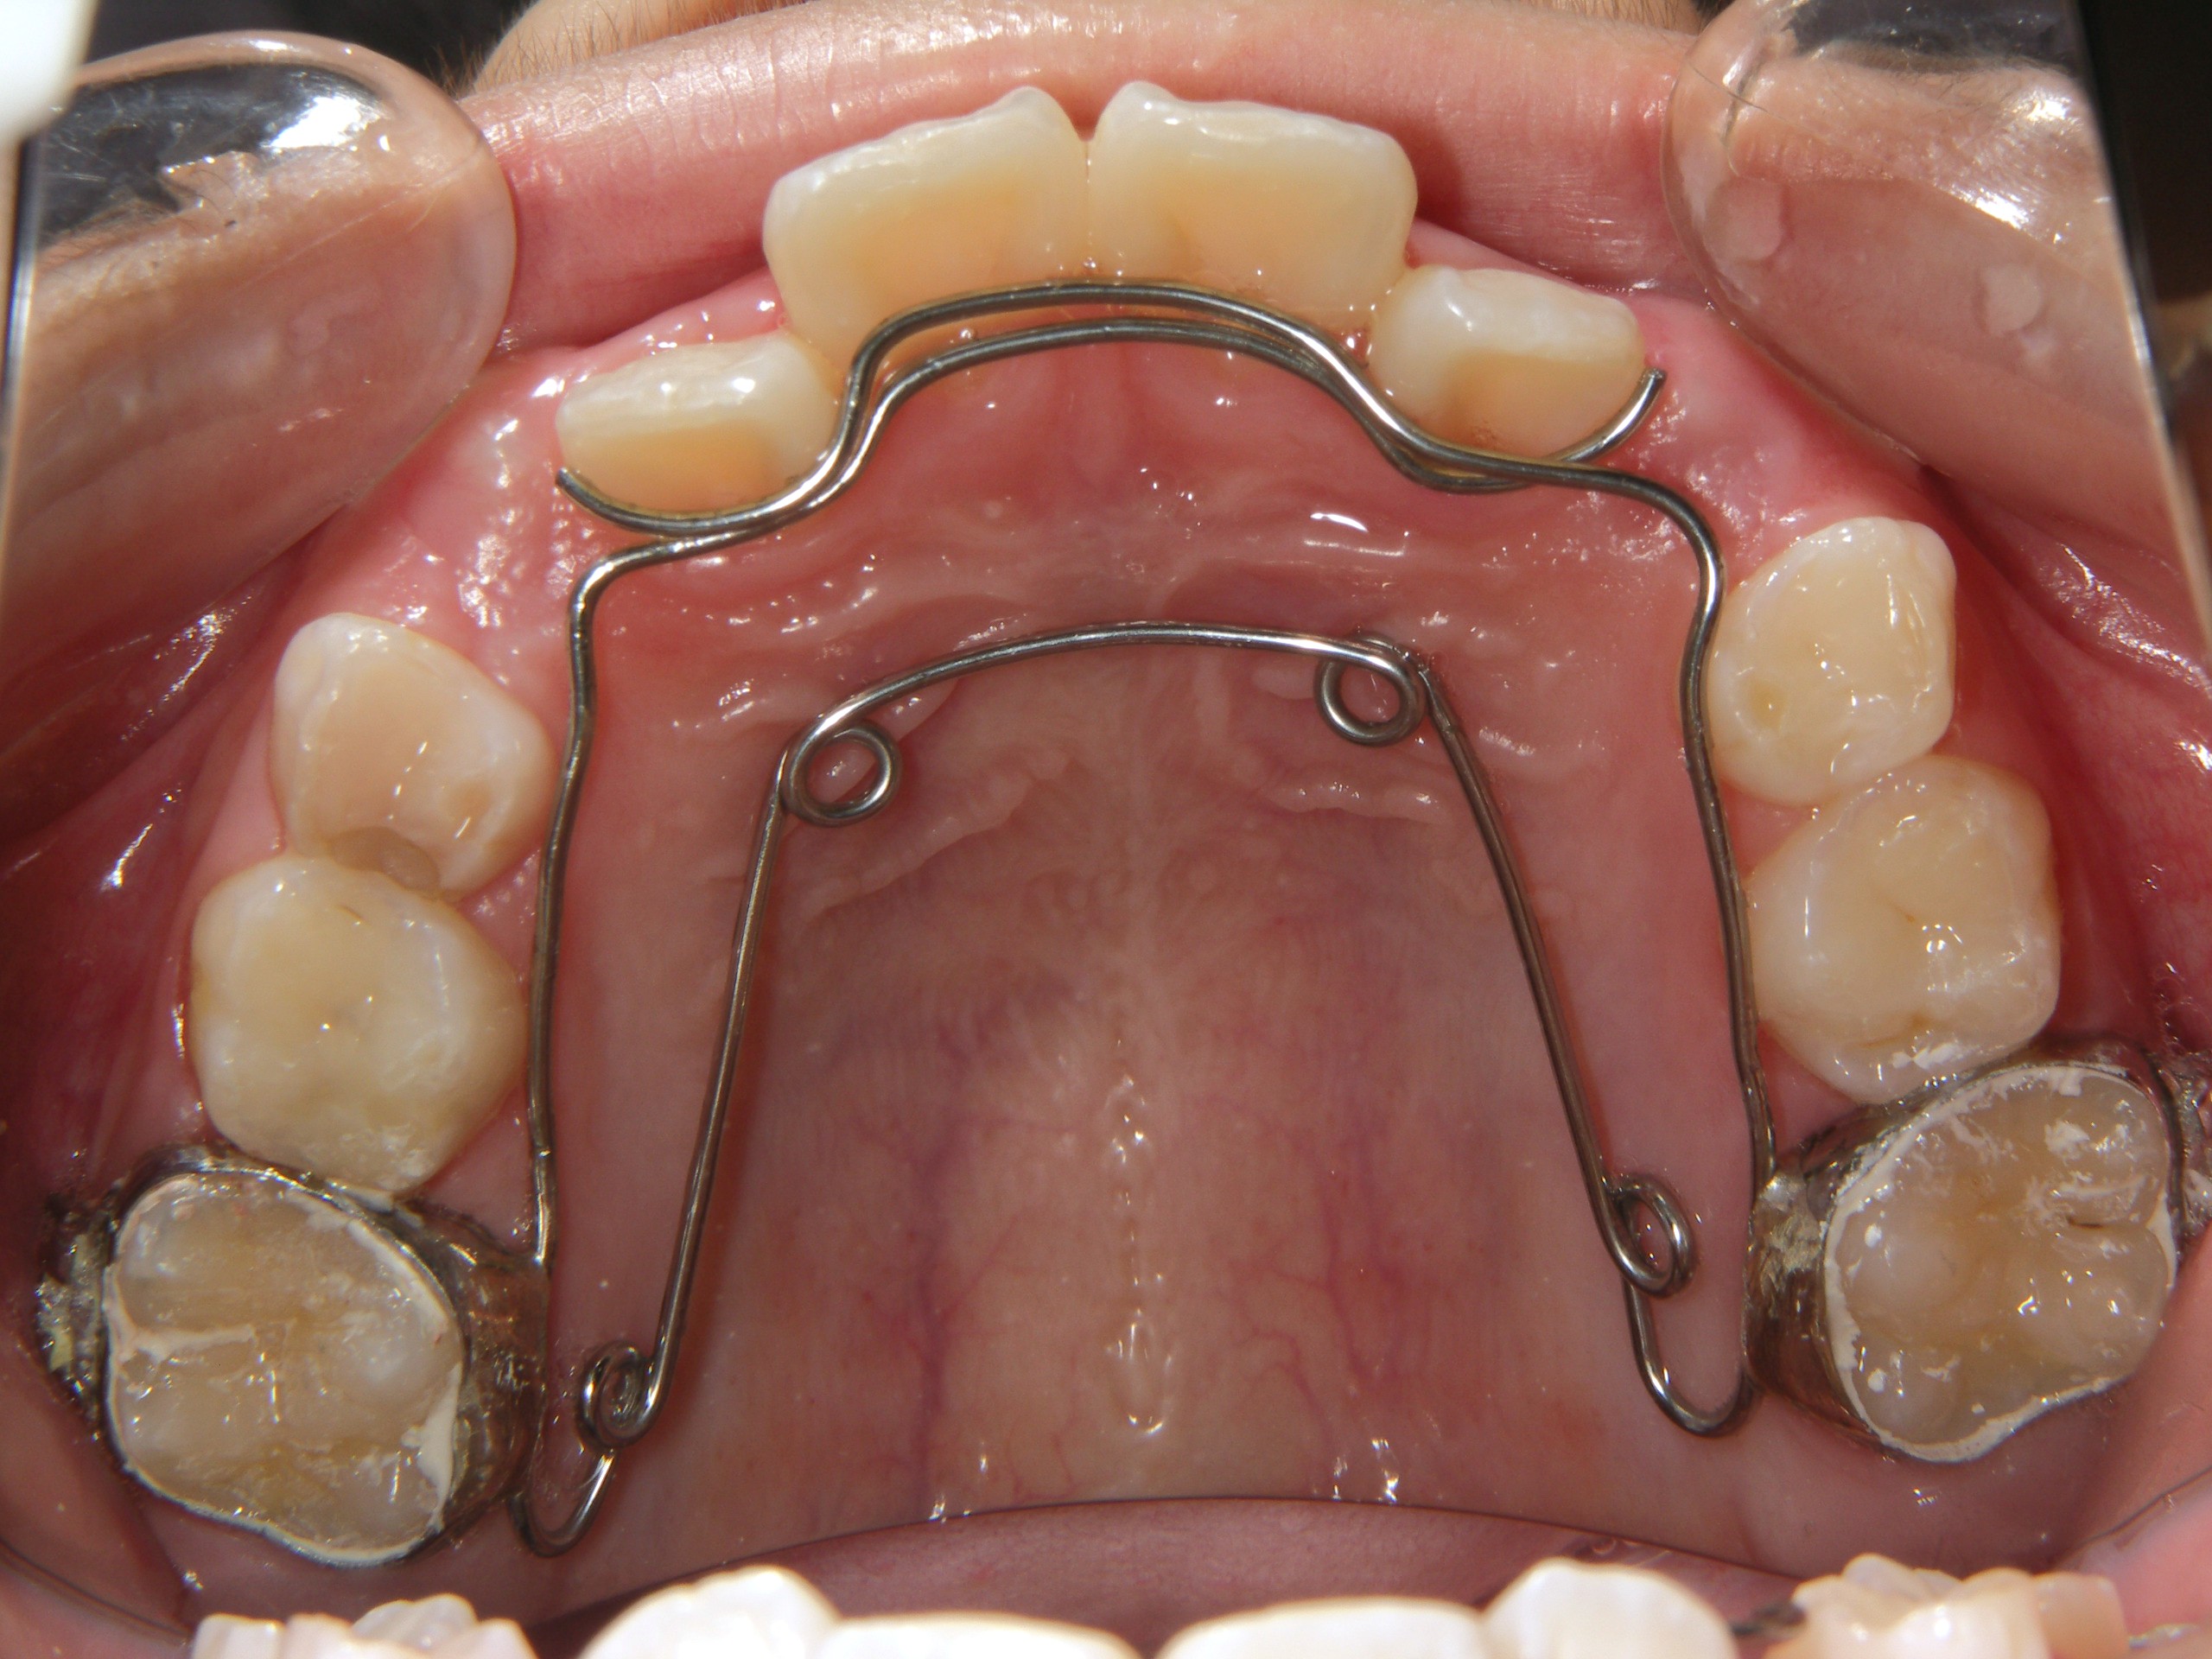

第1期治療終了時

顔貌写真

口腔内写真

治療結果

上の前歯のデコボコが改善

上の歯の狭さが改善

目標の永久歯萌出スペースを確保

第2期治療へ移行

上の前歯の裏側に保定装置(Fixリテーナー)を装着し、全ての永久歯萌出後に全顎矯正を行い、全体的な咬み合わせの調整を行います。

経過観察期間:2年7か月